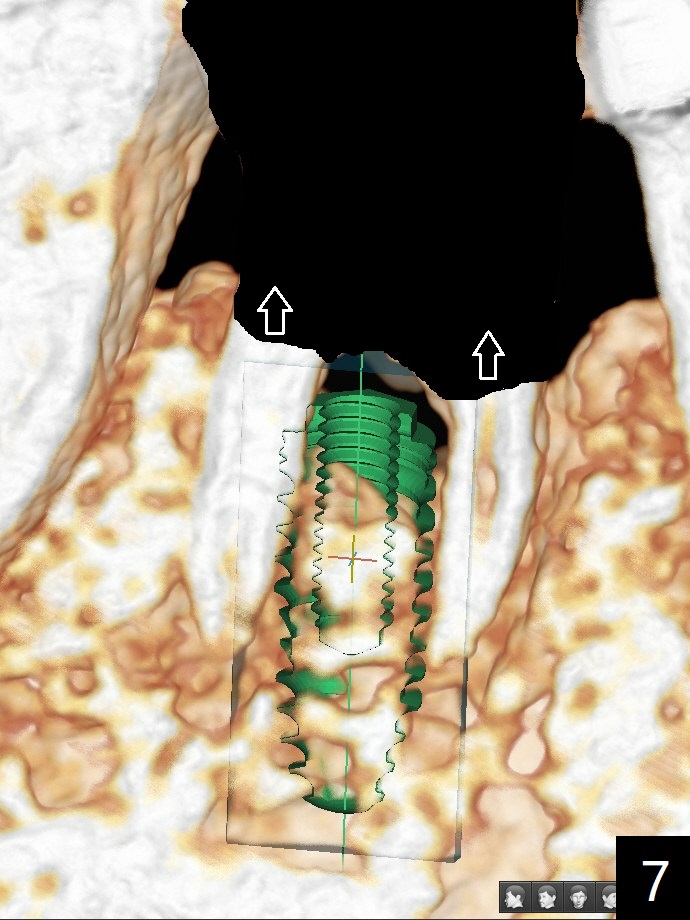

A 65-year-old man has nocturnal pain associated with #30 lingual furca caries and gingival recession (Fig.1,2). PRF (x2) and sticky bone will be used to repair the lingual soft and hard tissue defects. CT shows the submandibular fossa (Fig.3 <), dictating a short implant 10 mm, Fig.4). To place the implant in the septum (Fig.3 S), the coronal portion of the tooth is removed (Fig.5 black area) so that the roots are able to keep the osteotomy without deviation (Fig.6 red arrow). It is possible to place the implant in a trajectory mesiodistally (Fig.7 in fact after root extraction (arrows)). To prevent buccolingual deviation, a small implant (4 mm in diameter) is designed so that it will NOT touch the buccal (B in Fig.8) or lingual (L) plates. The bone density of the cortex and medulla is 2000 and 1400 units, respectively. To reduce the chance of implant fracture because of the narrow diameter in function, an implant with Titanium V will be used.